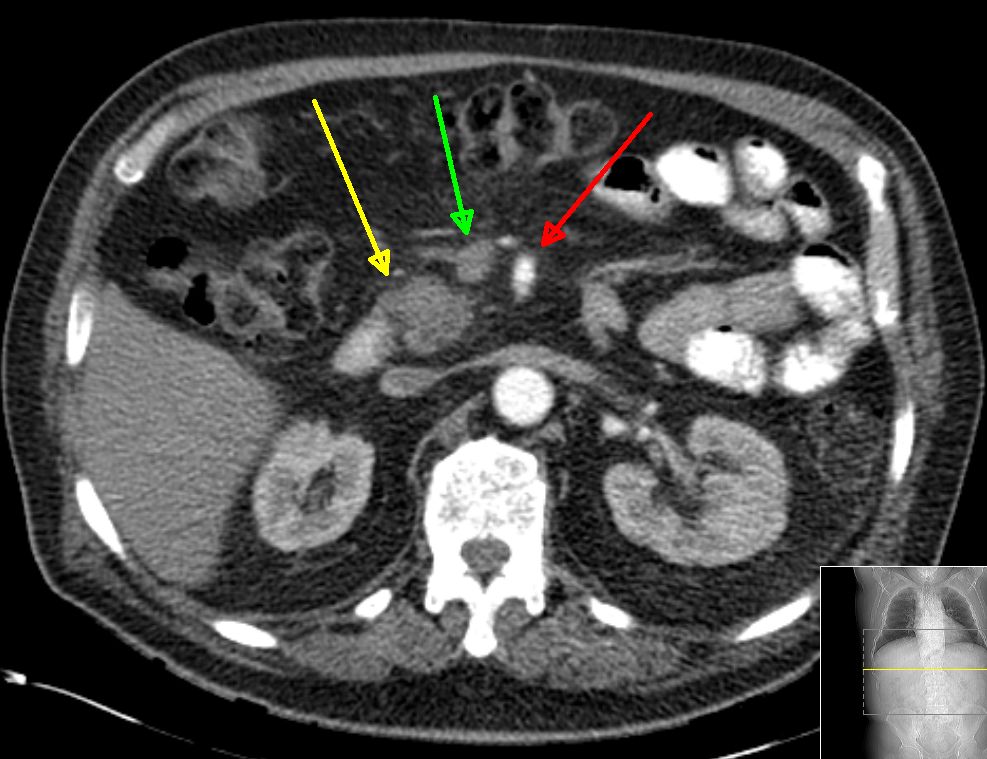

Operables Pankreaskopfkarzinom

|

Karzinom (gelber Pfeil), V. cava und V. mesenterica superior ist frei (grüner Pfeil), A. mesenterica superior ist frei (roter Pfeil)